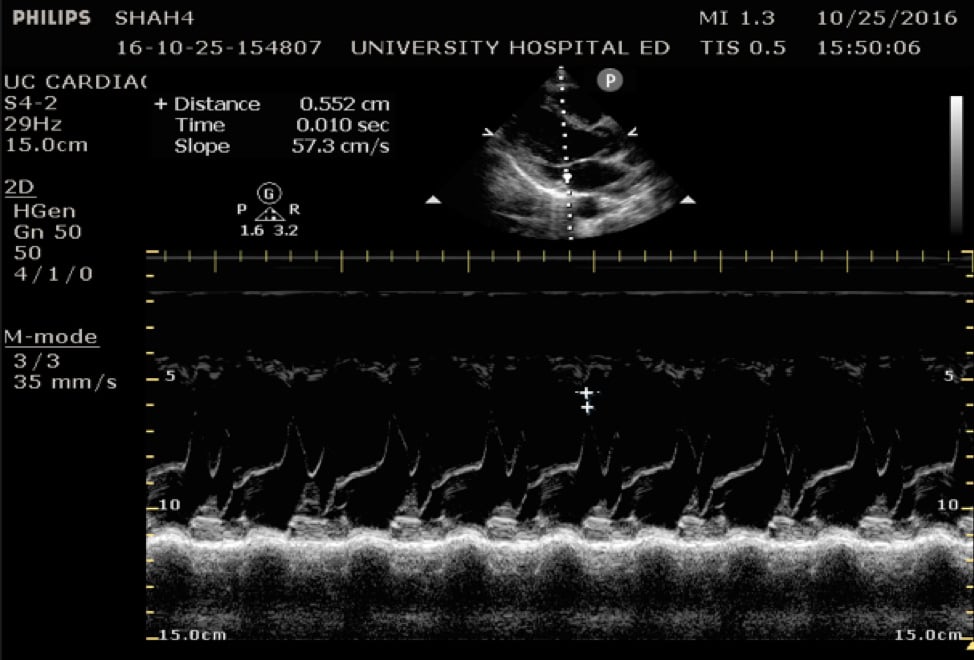

EPSS

In the parasternal long view, an M-mode line is placed through the anterior mitral leaflet. The distance is between the leaflet tip and interventricular septum is measured during the point in early diastole where the tip of the leaflet is closest to the septum. (Figure 5) A value of >7mm is highly suggestive of depressed cardiac contractility or low EF. (Figure 6) Note that this measurement is invalidated by the presence of valvular pathology or left ventricular/septal hypertrophy. This method is also not valid for assessing for hypercontractility.

Figure 5. Image of normal EPSS measurement measured from the tip of the anterior mitral valve leaflet in diastole to the interventricular septum

Figure 6. Abnormal EPSS measurement